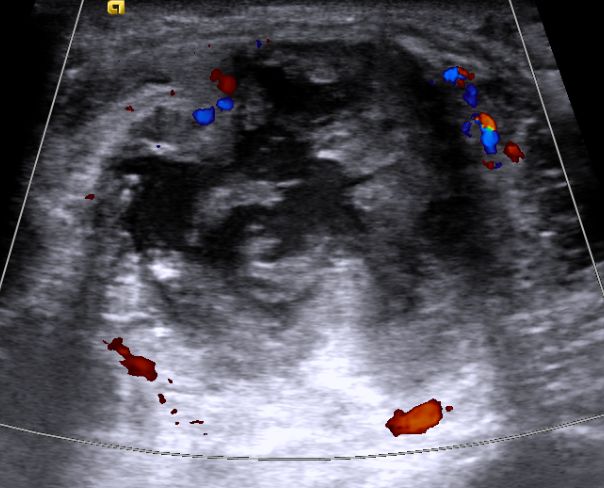

| Ulna | 56-jähriger Mann mit Plattenepithelkarzinom des rechten Hauptbronchus T4 N2 M1. Schmerzhafte Schwellung an der Innenseite des rechten proximalen Unterarms. Deutliche Sklerosierung der Ulna.

![]() |

Das Ultraschallbild zeigt einen zentral erweichtenWeichteitumor

mit randlicher Gefäßerweiterung. Weichteiltumor.![]() | Hüftpfanne | |